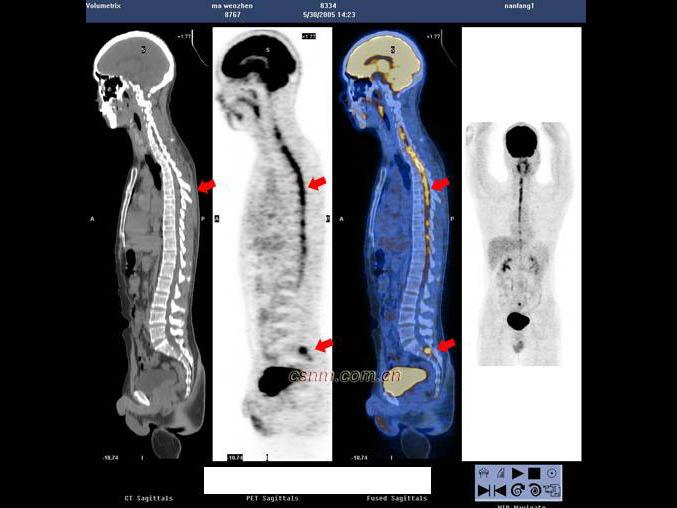

[单选题]男,7岁,2岁时因头痛而就诊,MRI示脑积水、颅内(小脑蚓部及蝶鞍)见多发恶性肿瘤,临床诊断为髓母细胞瘤。未行手术治疗,多年来一直行放、化疗治疗,最后一次化疗1个月前结束。因腹胀、恶心、呕吐1周而就诊,CT示:双侧侧脑室充满肿瘤病灶,PET/CT全身显像如图。正确的描述是 ( )A.肿瘤复发并沿双侧侧脑室弥漫性浸润B.肿瘤同时向双侧丘脑及豆状核浸润、侵犯;蝶鞍内块状高代谢病灶,考虑为转移灶C.脑干及颈段、胸段、上腰段脊髓内见长条状高代谢病灶,考虑为肿瘤向脑干及大部分脊髓播散、种植转移D.正常情况

[多选题] 男,7岁,2岁时因头痛而就诊,MRI示脑积水、颅内(小脑蚓部及蝶鞍)见多发恶性肿瘤,临床诊断为髓母细胞瘤。未行手术治疗,多年来一直行放、化疗治疗,最后一次化疗1个月前结束。因腹胀、恶心、呕吐1周而就诊,CT示:双侧侧脑室充满肿瘤病灶,PET/CT全身显像如图。正确的描述是()。A . 肿瘤复发并沿双侧侧脑室弥漫性浸润B . 肿瘤同时向双侧丘脑及豆状核浸润、侵犯;蝶鞍内块状高代谢病灶,考虑为转移灶C . 脑干及颈段、胸段、上腰段脊髓内见长条状高代谢病灶,考虑为肿瘤向脑干及大部分脊髓播散、种植转移

A.肿瘤复发并沿双侧侧脑室弥漫性浸润

B.肿瘤同时向双侧丘脑及豆状核浸润、侵犯;蝶鞍内块状高代谢病灶,考虑为转移灶

C.脑干及颈段、胸段、上腰段脊髓内见长条状高代谢病灶,考虑为肿瘤向脑干及大部分脊髓播散、种植转移

D.正常情况下脊髓内无明显放射性浓聚,当出现椎管内肿瘤转移则可表现为

F-FDG明显浓聚,呈“辫子征”